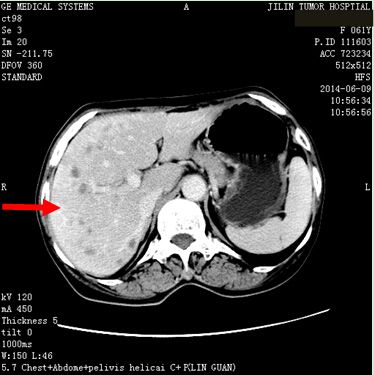

患者任某,女,60岁,患者因刺激性咳嗽3个月,右上腹部疼痛2个月于2014年4月11日就诊。入院后行肺增强CT、全腹增强CT;:左肺下叶支气管开口周围见类圆形肿块影,大小约为4.75×4.54cm,肿块包绕左肺下静脉及左肺下动脉干,肿块不均匀强化,左肺下叶支气管开口截断,左肺下叶内前基底段肺组织实变。左肺门见肿大淋巴结与肺门肿块融合。肝脏大小及形态未见确切异常,肝实质内弥漫性分布低密度肿块影,肿块融合成团,约占据整个肝脏,增强检查环形强化,选择病灶2.81×2.68cm,腹腔内见多个肿大淋巴结,融合成团,包绕邻近组织,较大约为3.21×2.57cm,左侧肾上腺见类圆形肿块影,大小约为2.49×1.99cm,增强检查略强化。明确诊断为:左肺下叶小细胞肺癌(T2aN1M1b)Ⅳ期,广泛期、左肺门淋巴结转移、 多发肝转移、腹腔淋巴结转移。符合我院正在进行的Ipilimumab联合EP治疗广泛期小细胞肺癌的III期临床研究,给予入组。于2014年5月1日开始给予EP方案化疗(VP-16,100mg/m2,157mg,d1-3;DDP,75mg/m2,118mg,d1),共给予化疗4周期,第3周期开始给予加用Ipilimumab单抗(10mg/kg),现患者已应用2周期,无明显严重不良反应发生。2周期后疗效判定:靶病灶1、左肺内病灶消失,2、左肾上腺转移病灶11.6×9.5=110.2,3、肝转移病灶11.3×9.1=102.83。靶病灶乘积之和213.03,疗效判定PR,非靶病灶:1、肝内其他转移病灶,存在,2、腹腔其他转移淋巴结,存在,疗效判定SD,总体疗效判定PR。现患者仍在继续用药中。

2014年6月9日 治疗后